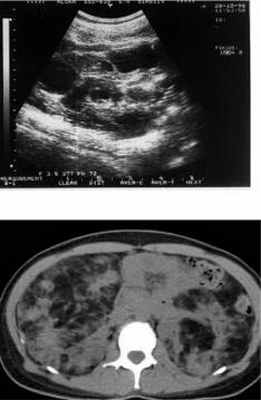

УЗИ. Кисты почки

На КТ множественные двусторонние образования в почках, содержащие жировую ткань – ангиомиолипомы.

Ангиомиолипомы и кисты. Редко - карциномы. Нарушения со стороны почек, как правило, появляются на 2-м - 3-м десятилетии жизни. Ангиомиолипомы при туберозном склерозе множественные, двусторонние и длительное время имеют бессимптомное течение.

Ангиомиолипомы больше 4 см в диаметре имеют тенденцию к спонтанному кровоизлиянию. Основными клиническими симптомами кровоизлияния из ангиомиолипомы: острые абдоминальные боли, падение артериального давления. Кисты почек при туберозном склерозе чаще небольшого размера, двусторонние. При увеличении размера кист развивается почечная недостаточность, появляется высокое артериальное давление.